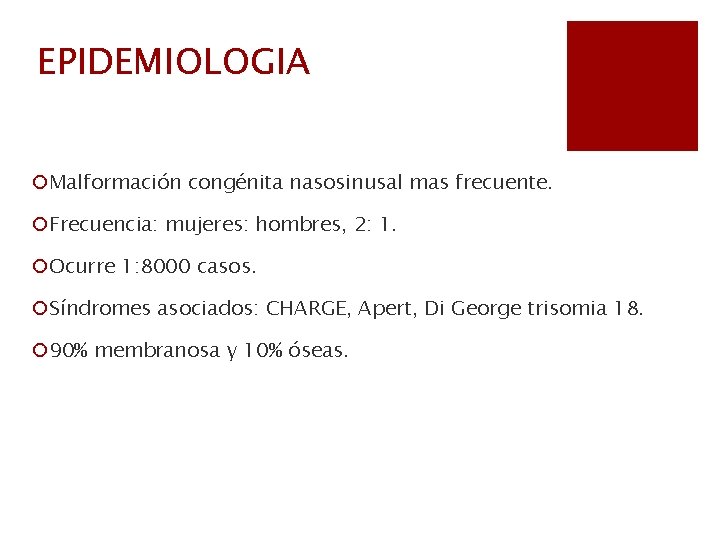

EPIDEMIOLOGIA ¡Malformación congénita nasosinusal mas frecuente. ¡Frecuencia: mujeres: hombres, 2: 1. ¡Ocurre 1: 8000 casos. ¡Síndromes asociados: CHARGE, Apert, Di George trisomia 18. ¡ 90% membranosa y 10% óseas.